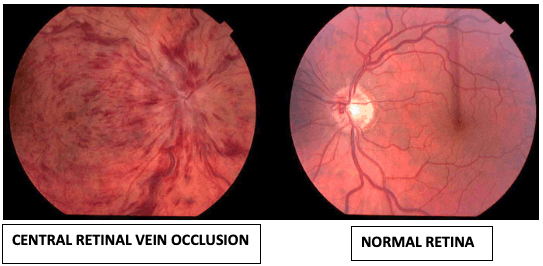

What is a Central Retinal Vein Occlusion (CRVO)?

The eye’s retina has arteries and veins which carry blood to and out of the eye. The retinas has one main artery and one main vein.

A central retinal vein occlusion is when the main vein of the retina is blocked. This causes blood and fluid to seep out into the retina.

The macular (central part of the retina) can also become swollen due to this blockage and cause distortion in central vision.

What are the symptoms of CRVO?

Central Retinal Vein Occlusion may cause the following symptoms:

- Sudden loss of vision

- Seeing floaters: usually due to bleeding into the vitreous gel of the eye

- Painful eye: this is not common but can occur due to very high eye pressure from glaucoma

Not all CRVO cases need active treatment and may only require observation. This is especially if the blood flow is not severely compromised. This type of central retinal vein occlusion is called a non-ischaemic CRVO.

In other cases, the blood flow is significantly blocked and this leads to poor circulation to the retina. This type of central retinal vein occlusion is called a ischaemic CRVO. In ischaemic CRVO, laser to the retina called panretinal photocoagulation is needed to reduce the oxygen requirement of the retina. This is needed to prevent abnormal blood vessels from growing in a process called neovascularization. Neovascularization can lead to serious complications such as vitreous haemorrhage (bleeding in the eye) and glaucoma (high eye pressure).

In some cases, CRVO may cause swelling in the macular (central part of the retina) called macular oedema. In such cases, medication injections in the eye called anti-VEGF injections may be recommended. Occasionally, steroid injections may also be used.